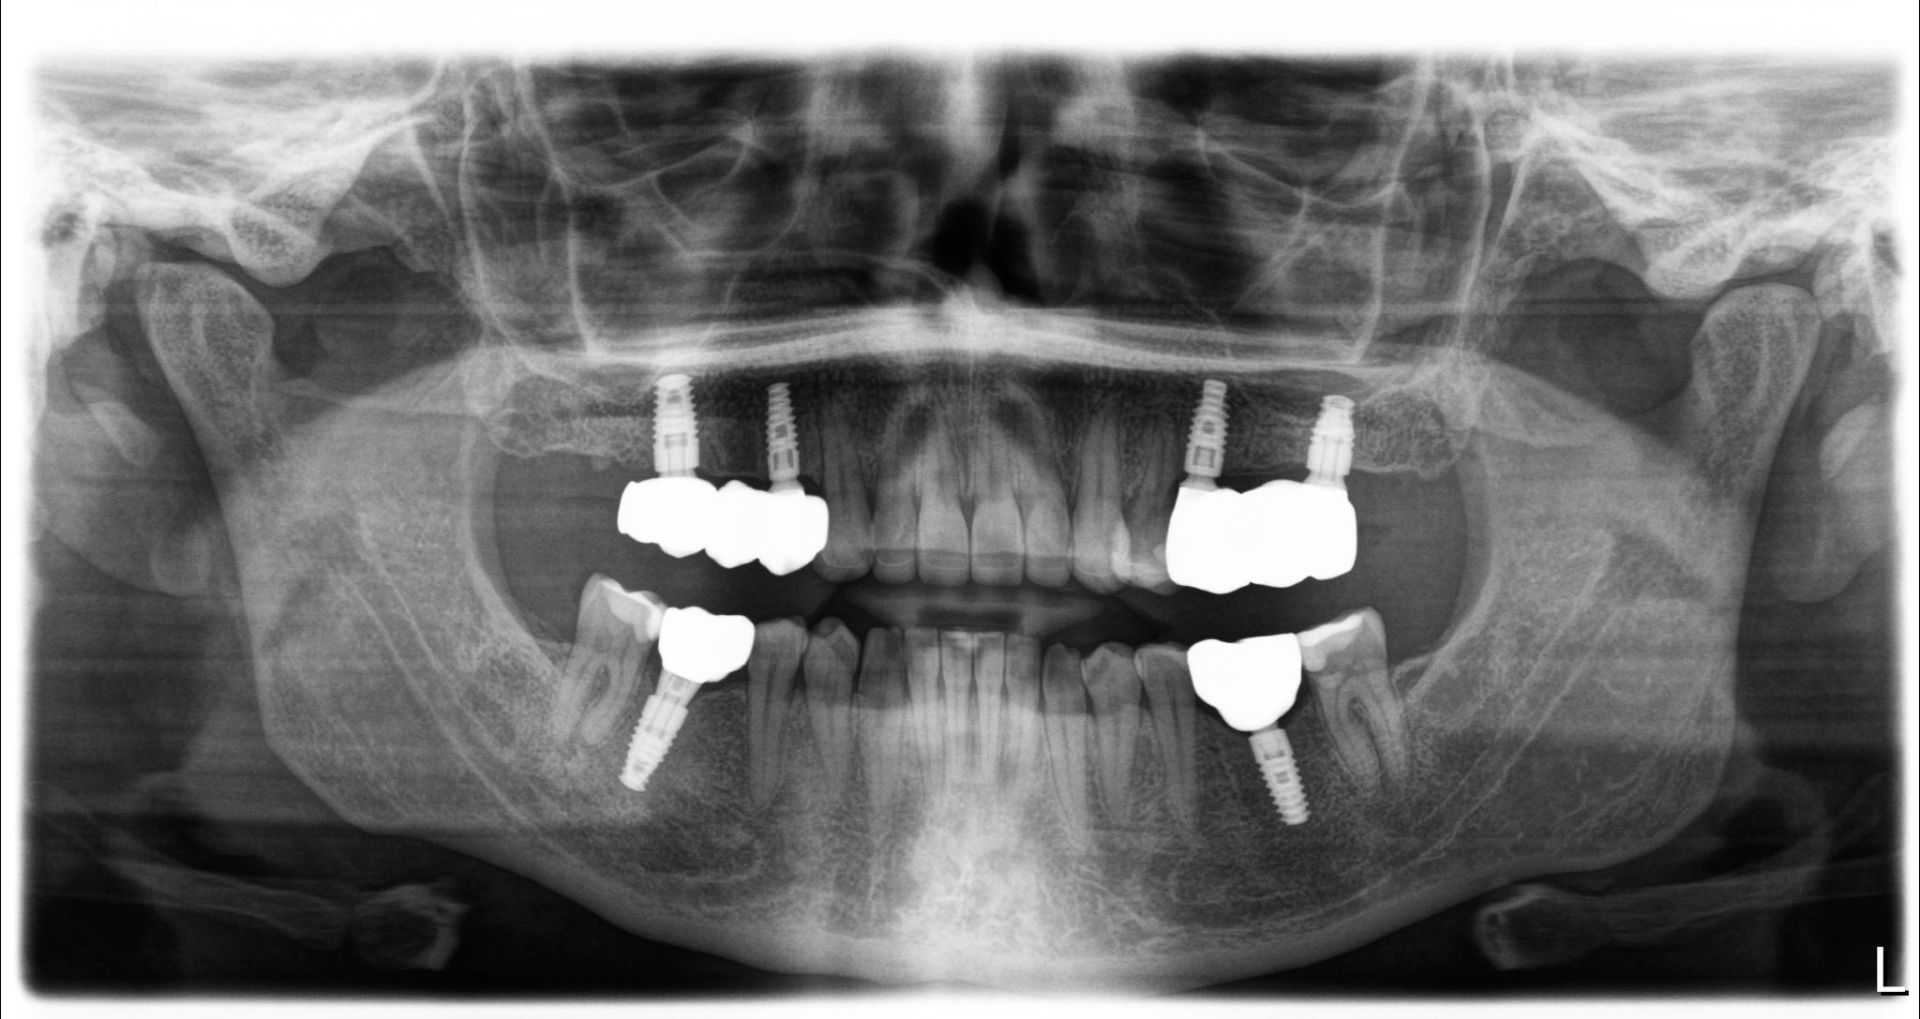

After